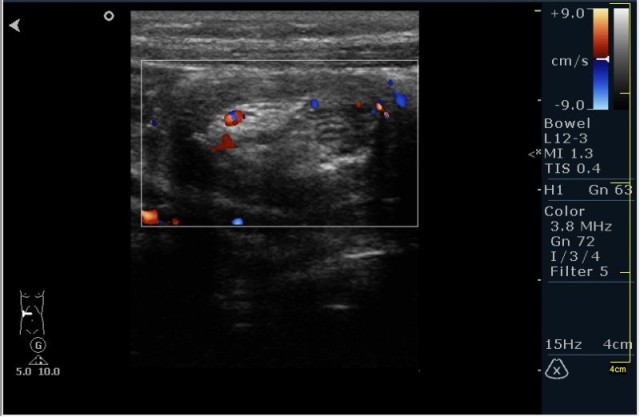

Ребёнок с болями в животе.

инвагинация! :!:

На представленных сонограммах определяется типичная "мишень" или "кокарда" (7ая и 8ая сонограмма сверху), которая при продольном сканировании превращается в "телескоп" (сонограммы 3 & 4). Все это указывет на инвагинацию кишечника (илео-цекальную). Причиной явилось лимфаденопатия брыжейки (которую вы указали). Увеличеные лимфоузлы вместе с инвагинатом хорошо различимы в просвете толстой кишки.

Уважаемые коллеги! Без сомнения имеет место илео-цекальная инвагинация.увеличенные овальные лимфоузлы, да еще такими гроздями характерны для мезаденита.Все зависит от развертывания клинической симптоматики.

Вариант 1- развите острого мезаденита спровоцировало инвагинацию.

вариант 2 - повторяющиеся эпизоды инвагинации привели к лимфоаденопатии.